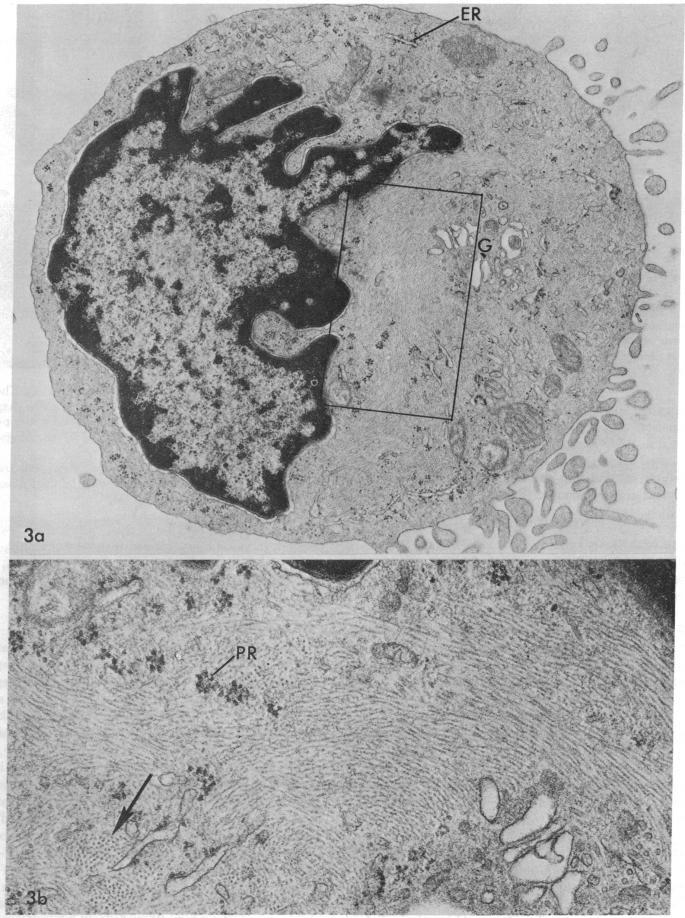

The vast majority of human lymphoid neoplasms examined to date have been associated with a proliferation of bone marrow-dependent (B) lymphocytes. In an effort to delineate human tumors of T-cell (thymusdependent) lineage, use was made of the peripheral blood leukocytes of sixteen subjects with various forms of mycosis fungoides. The abnormal cells in the circulation of these patients are morphologically identical to those that infiltrate their nodes and skin. On electron microscopy, such neoplastic lymphocytes (Sézary cells) had "cerebriform" nuclei and an abundance of cytoplasmic fibrils not described heretofore. Sézary cells were nonadherent and nonphagocytic and usually responded to stimulation with phytohemagglutinin, refuting earlier suggestions that the cells represent monocytes or histiocytes. In contrast to chronic lymphocytic leukemia lymphocytes, the Sézary cells lacked surface immunoglobulin and receptors for complement. Ultrastructural analysis identified Sézary cells in the center of directly formed rosettes (E-rosettes) characterizing the behavior of T lymphocytes in this test. Though some Sézary cells lacked both T and B cell-surface properties, in general, these observations support the view that the Sézary cell is a neoplastic variant of a thymusderived lymphocyte.